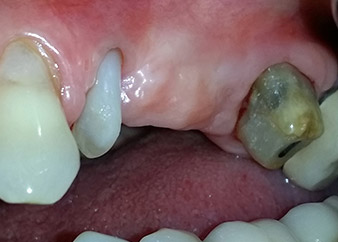

A 58-year-old female patient complained of pain and increased mobility of her bridge abutment tooth 24. Periodontal inflammation was present with pocket depths of 7 mm mesiobuccally and more than 12 mm distally, as well as third-degree furcation involvement. Moreover, the radiograph revealed an extensive periodontal lesion around the apical region of the (alio loco) endodontically pretreated tooth 24 (Fig. 1).

One month later, on the day of surgery, pain and inflammation at tooth 24 were minimal, but mobility of Miller class 2 was still present. After opening the flaps and cleaning the periapical and peri radicular infected tissue, the extent of the bone defect became obvious (Figs. 2 and 3).

At the buccal root, all vestibular and distal bone was missing. Attachment was essentially restricted to the palatal root, underlining the preliminary poor prognosis. Tooth 27 also showed a reduced horizontal attachment and a minimal apical rarefaction (cf. Fig. 1) without clinical symptoms.